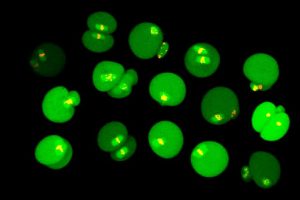

L’infertilité féminine liée à l’âge est expliquée par un défaut dans la chorégraphie du partage des chromosomes dans les ovules lors de la division cellulaire. Des chercheurs du Centre de […]

3 avril 2017 - Recherche, UdeM Nouvelles